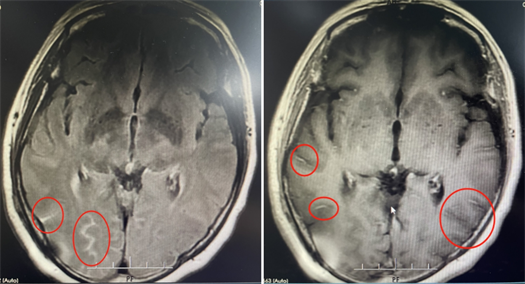

广东三九脑科医院神经内一科副主任匡祖颖:她的颅内压增高,不但导致对旁边的脑组织进行挤压,同时引起在脑袋里形成比较长的颅神经损伤,包括视力的下降、听力的损伤等一系列不可逆的神经损伤。

尽管立即采用了抗真菌治疗但梅姨在住院期间

她的左眼还是差点瞎掉,光感丧失

随后医生紧急为梅姨进行了手术

术后再经过一系列对症治疗

梅姨头痛症状完全好转,

左眼视力恢复正常